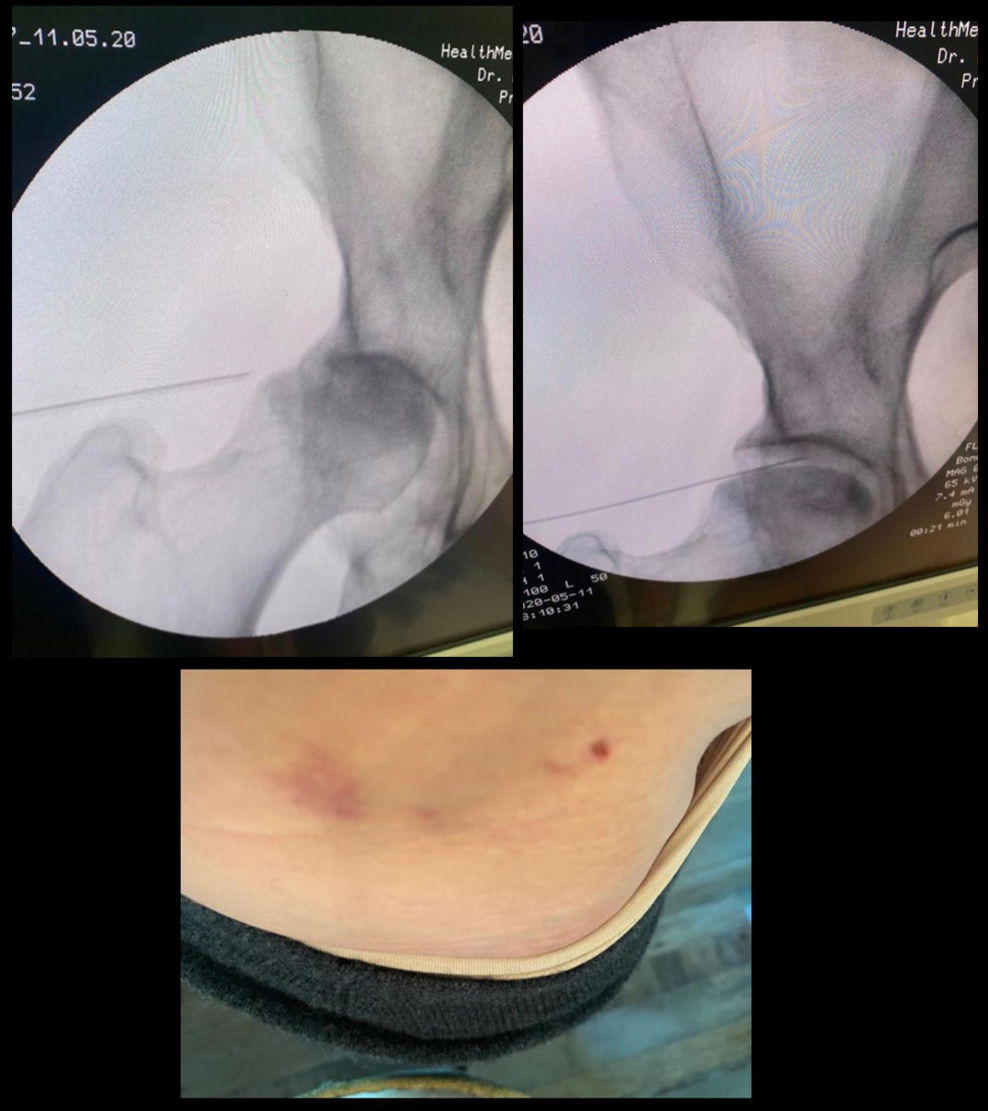

Selon un de nos fidèle lecteur qui est du métier, les clichés que l'on voit avec l'aiguille sont des images de sa hanche. Hanche qui d'après lui est en très mauvais état et qui nécessitera certainement une prothèse :-( Il ajoute qu'elle a du beaucoup en souffrir...